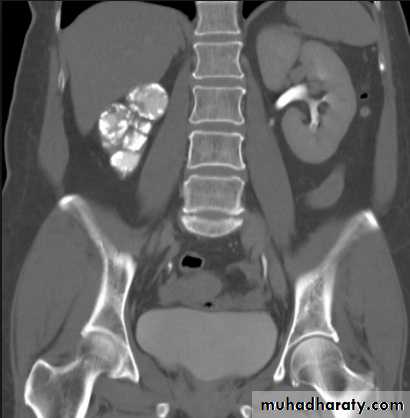

CT scans used in some hospitals during acute renal stone-Non contrast CT sensitively identify calculi and non opacified collecting system down to the level of obstruction. it has a sensitivity of 97% and specificity of 96% for detection of ureteral calculi

-Principal feature is dilatation of the pelvicalyceal system and ureter.

• The degree of dilatation depends on chronicity (long standing obstruction=more dilatation).

• The dilatation is down to the level of pathology

- Over 90% of calculi are radiopaque on plain films and virtually all on CT as very sensitive for detection of calculi, even those that appear radiolucent on plain film.- Most of these stones are a mixture of calcium oxalate and phosphate.